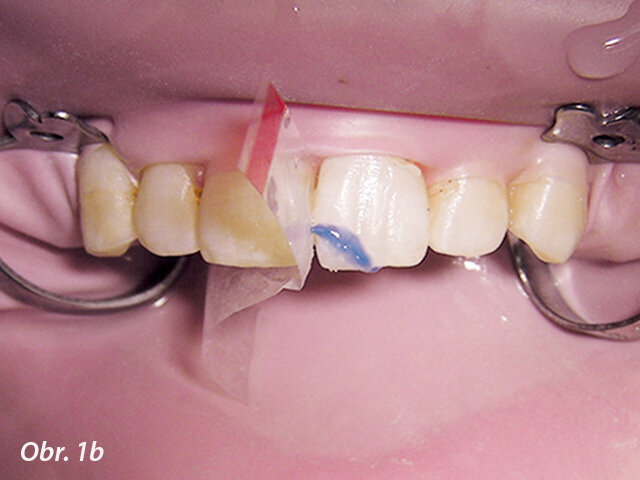

Obr. 1b, c: Po připojení obou fragmentů byl podél lomné linie vybroušen oblý schůdek, doplněn dalším kompozitem a zpolymerován na místě. To zvýší sílu spojení a lépe zakryje lomnou linii.

První, co je třeba udělat u jakékoliv korunkové nebo korunko-kořenové fraktury, je pokusit se najít odlomený fragment zubu. S moderní bondovací technologií je možné znovu spojit odlomený fragment se zbytkem zubu, což je esteticky nejlepší řešení. Ještě před připojením fragmentu zubu musí být tloušťka vrstvy zubu mezi pulpou a povrchem zhodnocena radiologicky a klinicky. Pokud zbývá alespoň 0,5 mm dentinu, není nutno místo překrývat ochrannou podložkou. Pokud je stanoveno, že zbytkový dentin je méně než 0,5 mm široký, je doporučeno překrýt oblast fraktury nejblíže u pulpy podložkou a tvarově přizpůsobit spojovací plochu fragmentu. Pokud byl fragment zubu držen v suchu, měl by být rehydratován v destilované vodě nebo slině po dobu 30 minut před spojováním, což zvýší vazebnou sílu (obr. 1a–c).